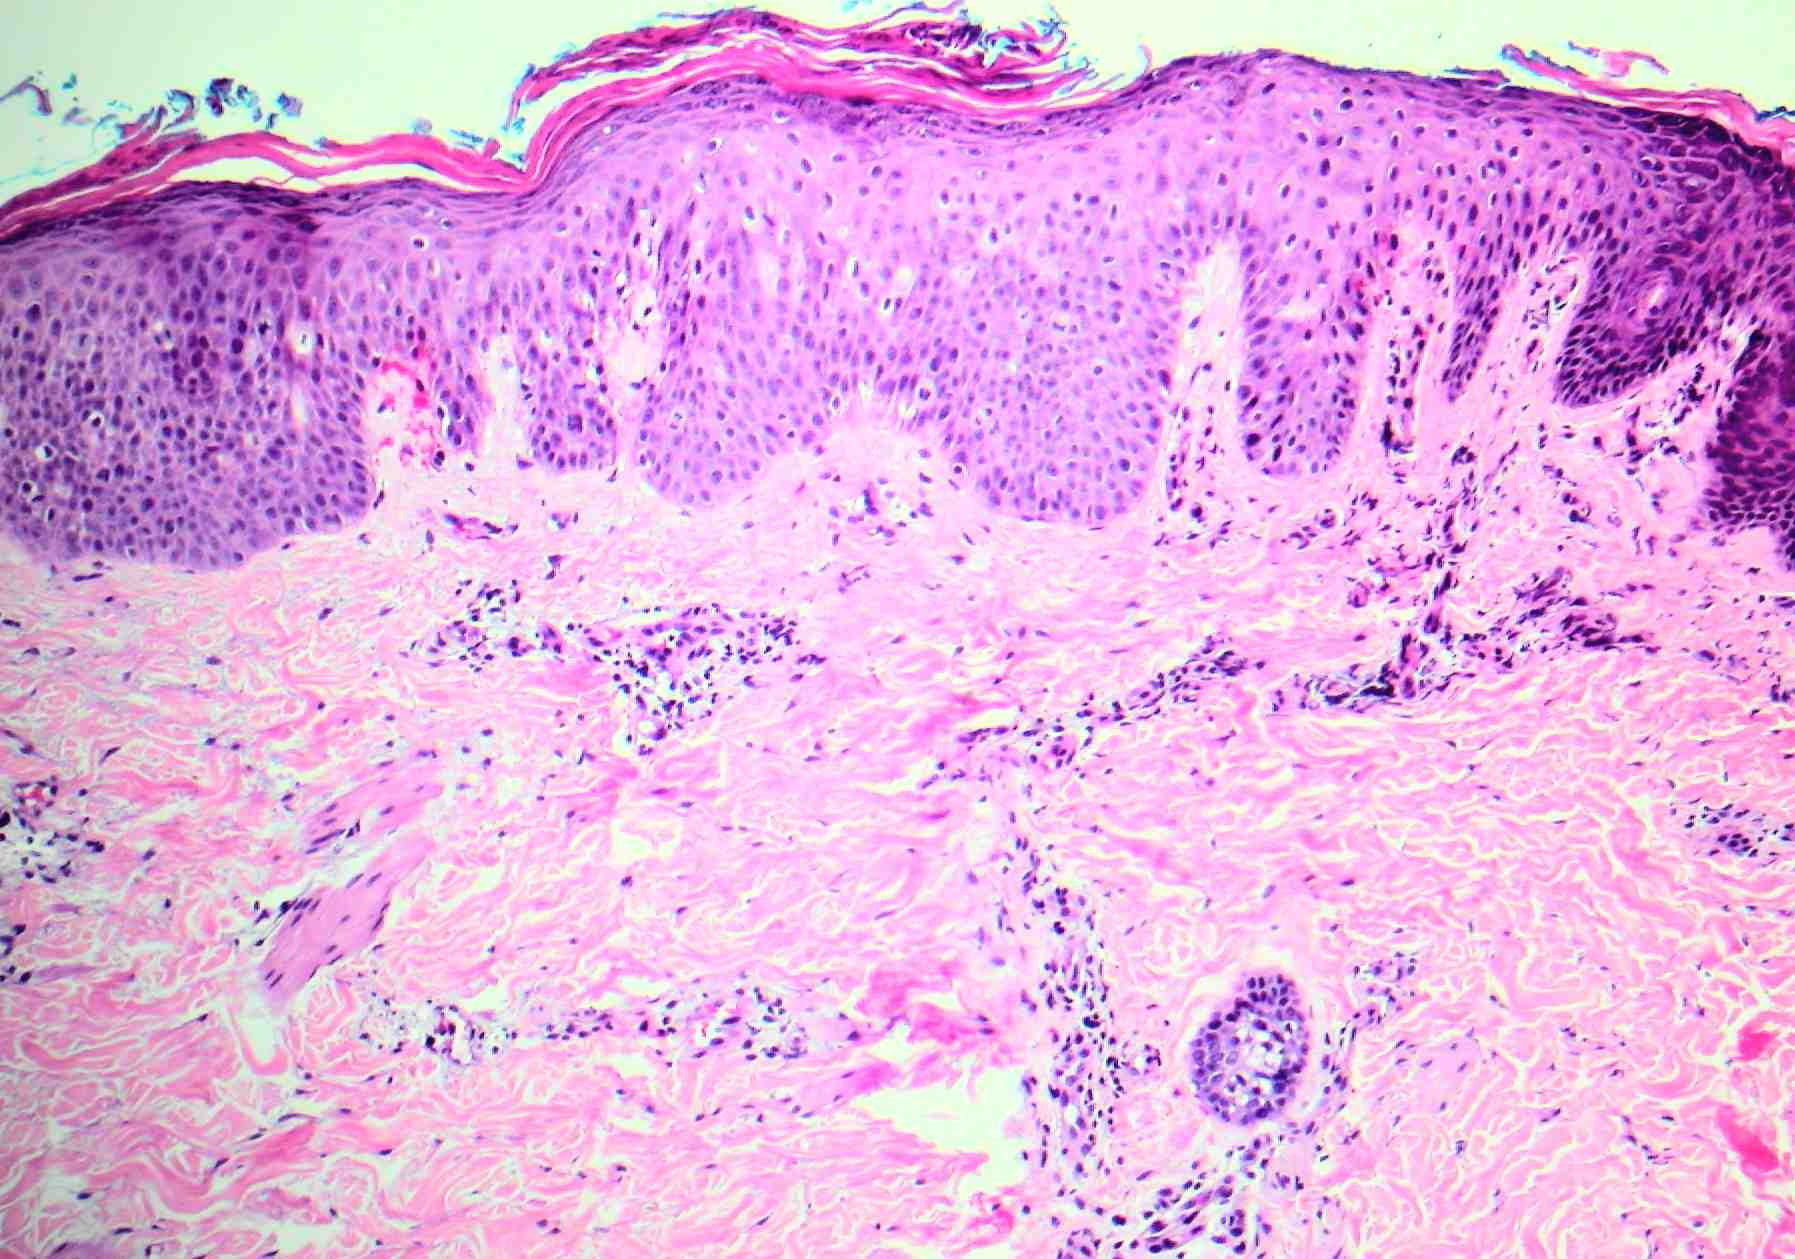

The underlying slightly edematous stratum malpighii contains a small number of neutrophils. Only a few spongiform pustules are formed. In some instances, a few acantholytic cells are found in the base of the pustule, most likely because of proteolytic enzymes present in the pustular contents. They may be partially attached to the epidermis or may lie free in the pustule among the neutrophils. The dermal papillae contain dilated capillaries and a perivascular infiltrate composed of neutrophils and a few eosinophils and mononuclear cells. |

Although subcorneal pustules occur in both pustular psoriasis and SPD, spongiform pustules occur only in pustular psoriasis. Some authors regard SPD as a variant of pustular psoriasis, but with the association to IgA gammopathies and squamous intercellular substance deposits of IgA, this view is discredited. |